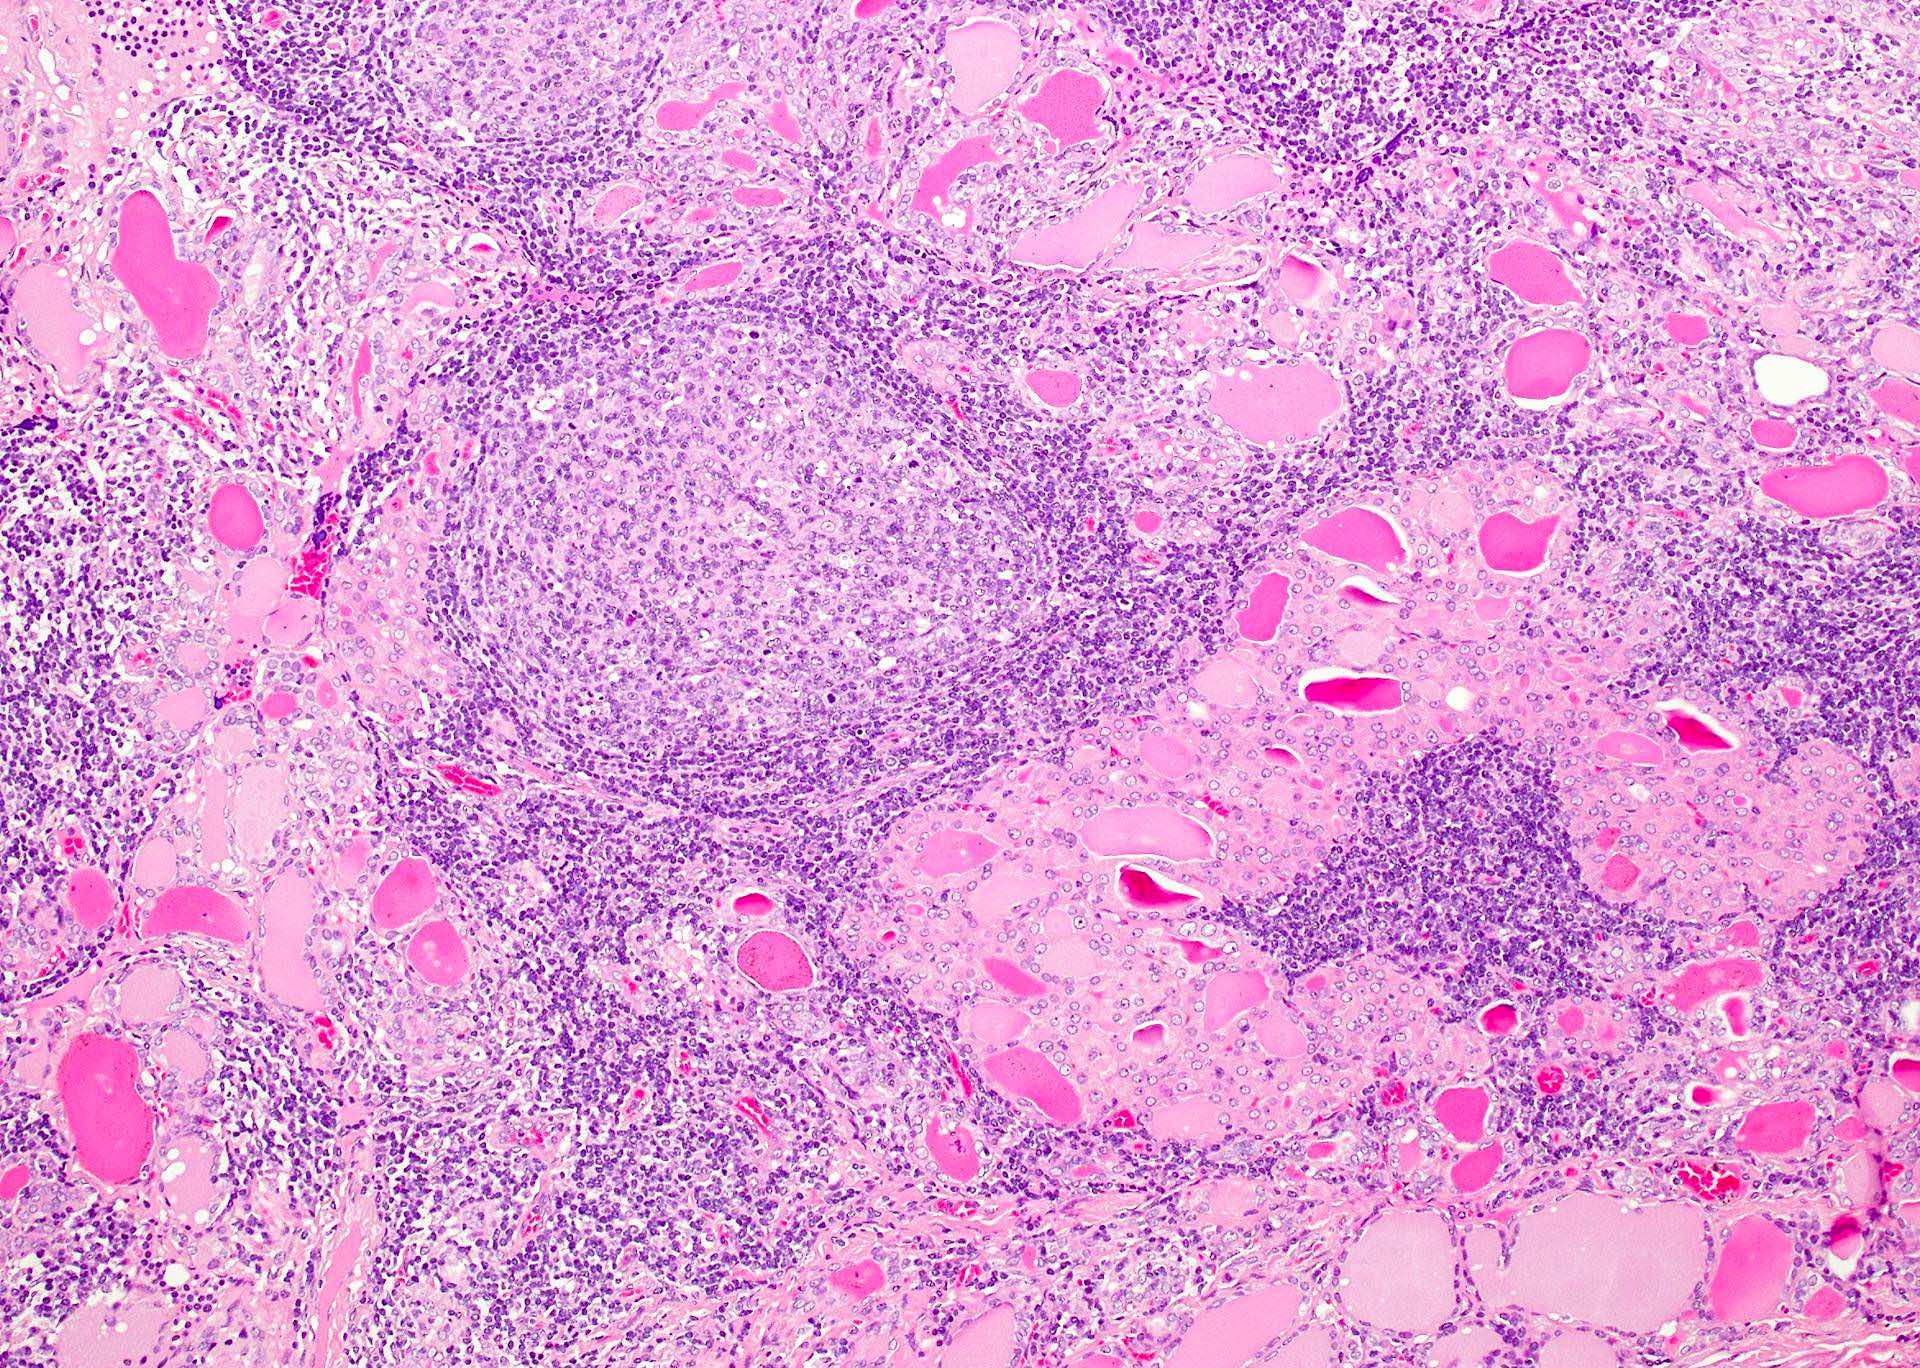

Hashimotos Thyroiditis Histology Bromelain Hashimoto's Thyroiditis Hashimoto’s thyroiditis is also known as chronic lymphocytic thyroiditis or autoimmune. Using enzymes can help with overcoming symptoms of hashimoto’s including fatigue, hair loss, and infections as well as with reducing thyroid antibodies. Hashimoto’s thyroiditis (ht) is a disease characterized by the chronic autoimmune inflammation of the thyroid tissue, which was. Among these potential scenarios, the most common one constitutes. Bromelain Hashimoto's Thyroiditis.

Hashimotos Thyroiditis Histology Bromelain Hashimoto's Thyroiditis Hashimoto thyroiditis is an autoimmune disorder that presents with or without signs or symptoms of hypothyroidism, often with a painless goiter, and is associated with elevated. Hashimoto’s thyroiditis (ht) is a disease characterized by the chronic autoimmune inflammation of the thyroid tissue, which was. Using enzymes can help with overcoming symptoms of hashimoto’s including fatigue, hair loss, and infections as. Bromelain Hashimoto's Thyroiditis.

Hashimotos Thyroiditis Histology Bromelain Hashimoto's Thyroiditis Hashimoto’s thyroiditis is also known as chronic lymphocytic thyroiditis or autoimmune. Hashimoto thyroiditis is an autoimmune disorder that presents with or without signs or symptoms of hypothyroidism, often with a painless goiter, and is associated with elevated. Hashimoto thyroiditis, also known as chronic autoimmune thyroiditis and chronic lymphocytic thyroiditis, is an autoimmune disease in which thyroid cells are destroyed via.. Bromelain Hashimoto's Thyroiditis.

Hashimotos Thyroiditis Histology Bromelain Hashimoto's Thyroiditis Hashimoto thyroiditis is an autoimmune disorder that presents with or without signs or symptoms of hypothyroidism, often with a painless goiter, and is associated with elevated. Among these potential scenarios, the most common one constitutes autoimmune thyroiditis (hashimoto’s thyroiditis (ht), graves’ disease,. Hashimoto’s thyroiditis is also known as chronic lymphocytic thyroiditis or autoimmune. Using enzymes can help with overcoming symptoms. Bromelain Hashimoto's Thyroiditis.